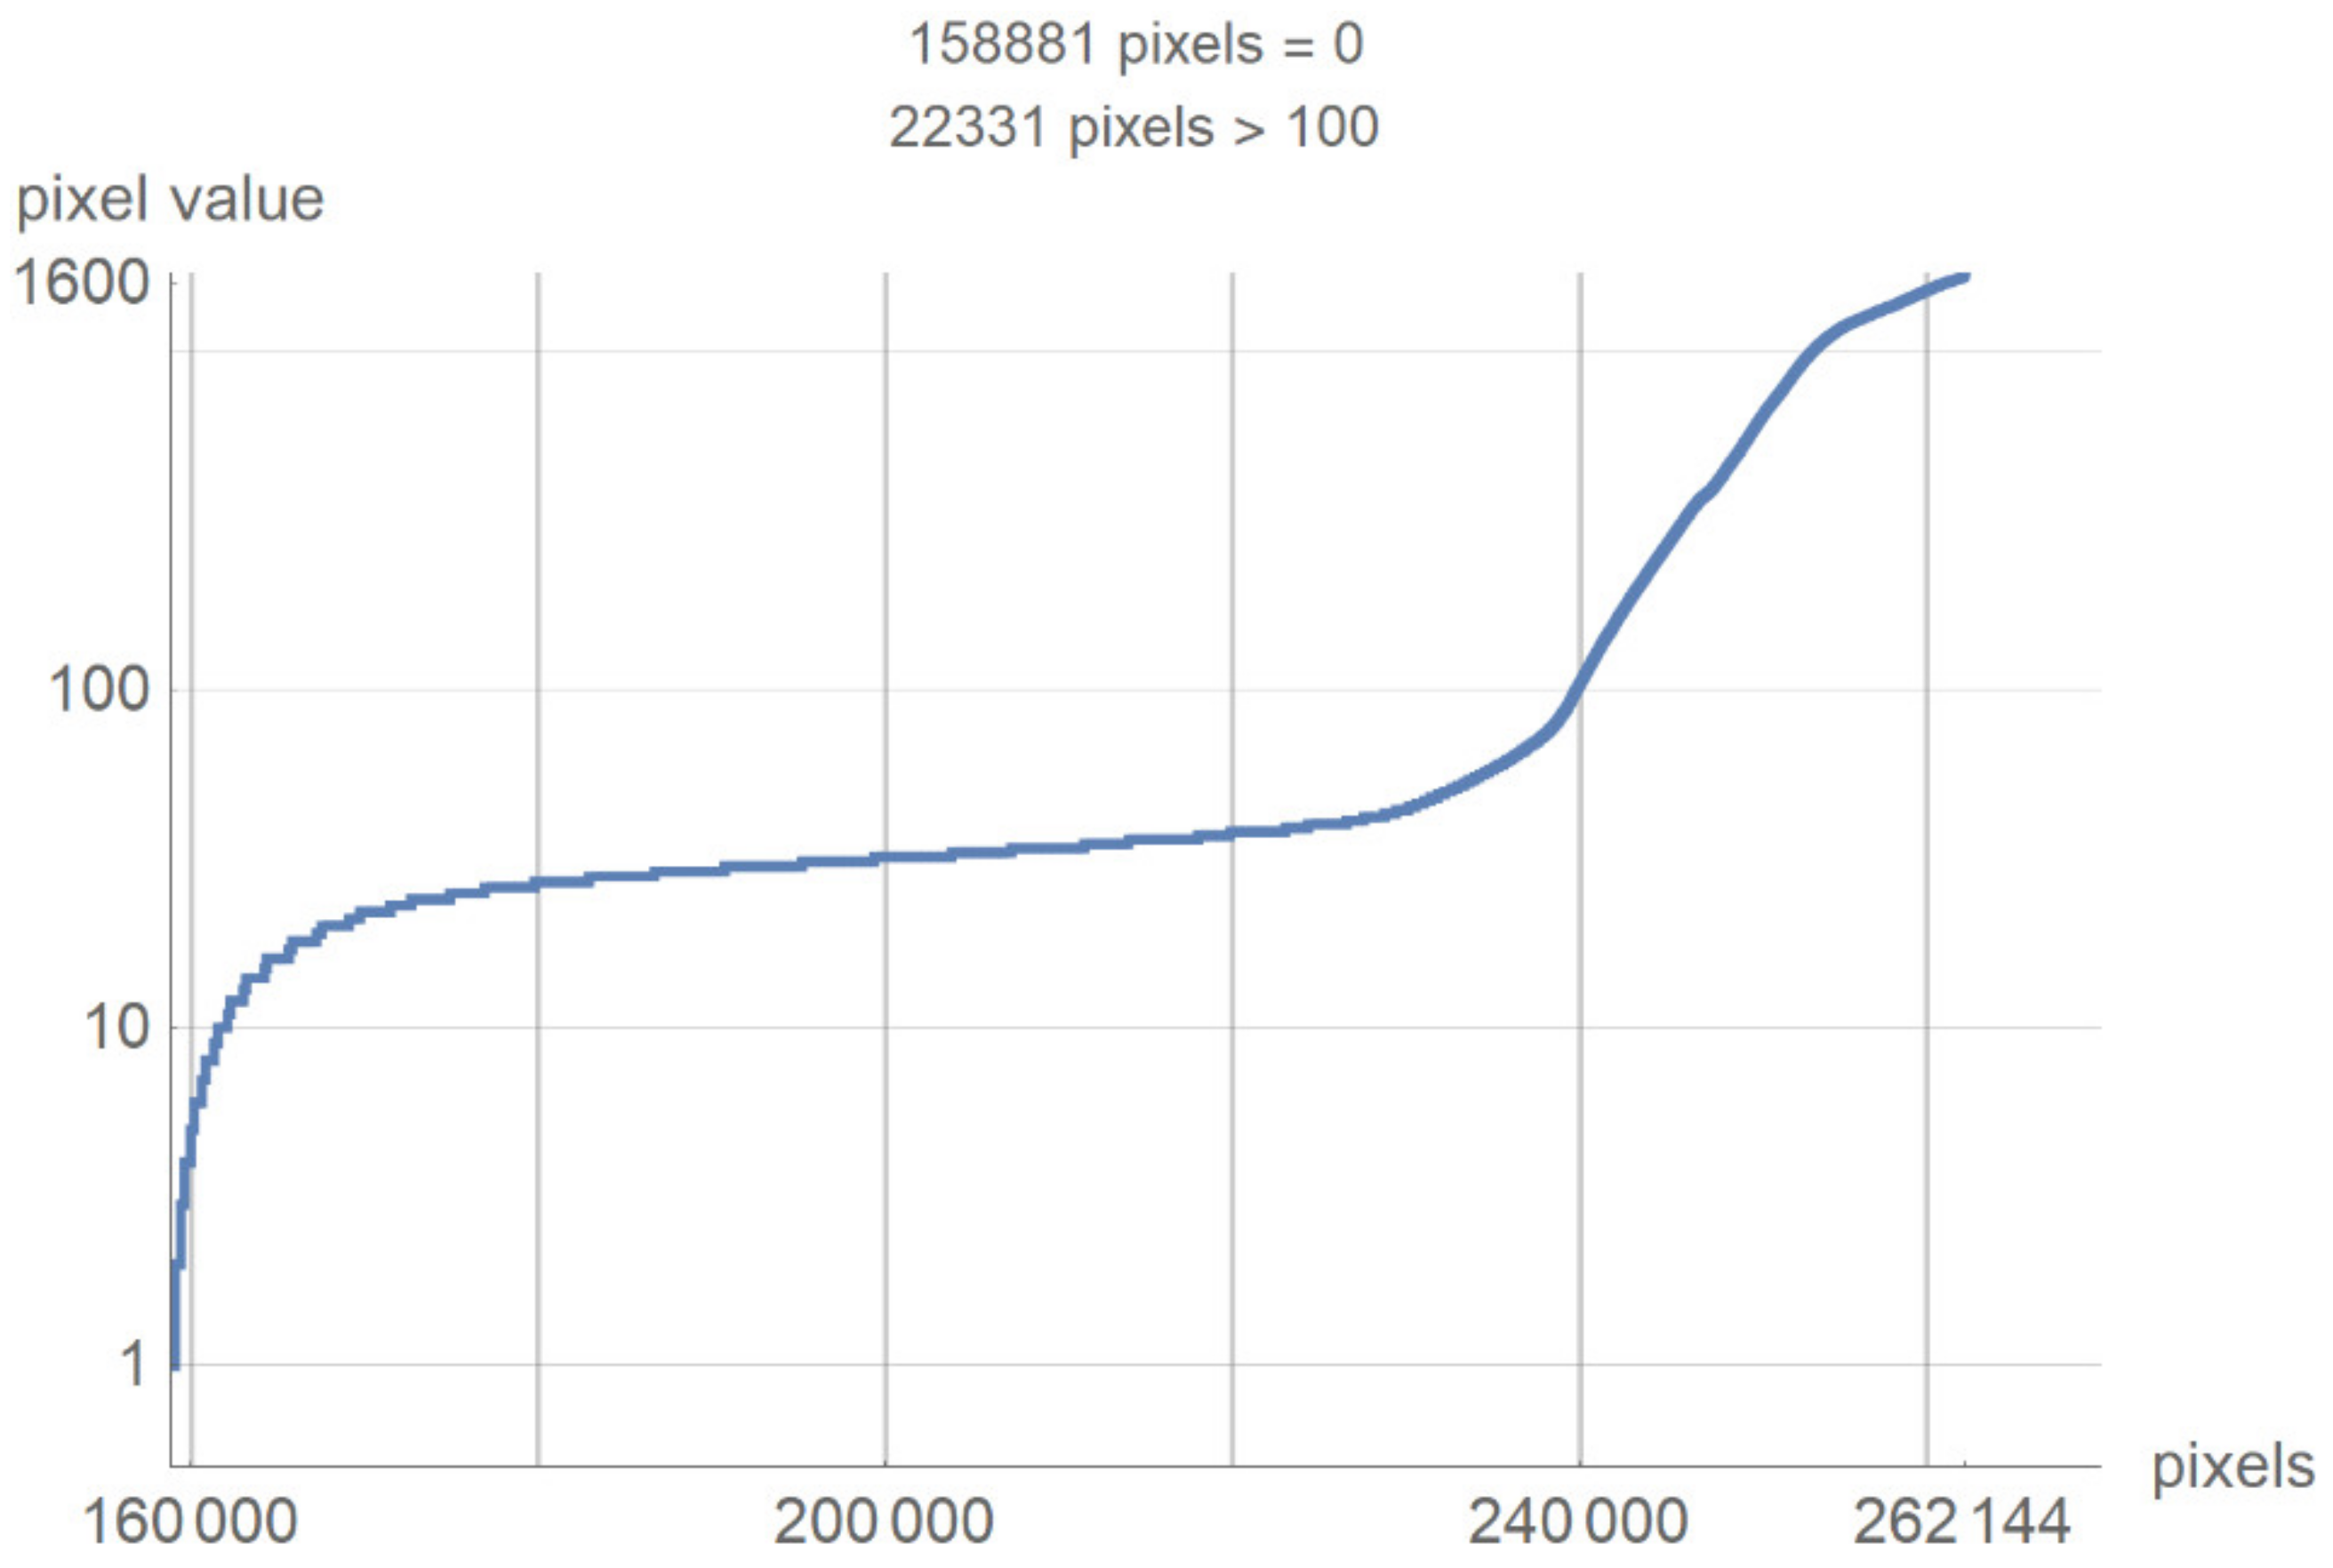

2.2. Smart Visualization Method (SVMI)

3.1. Technological Description